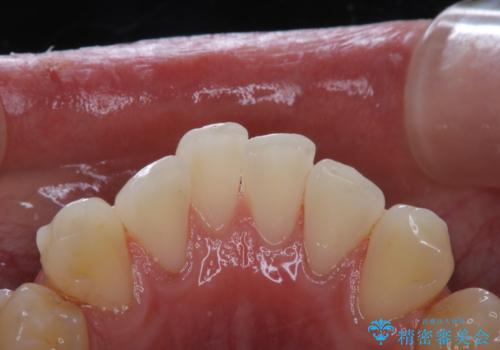

- インビザライン矯正治療中の方です。アタッチメントの周りの汚れが気になるとのことで、PMTC30分コースを行いました。

インビザライン矯正治療はマウスピースを長時間使用するため、歯石や汚れなどが付着したままだと、フィットが悪くなったり、口臭が強く出たりする原因につながることもあります。